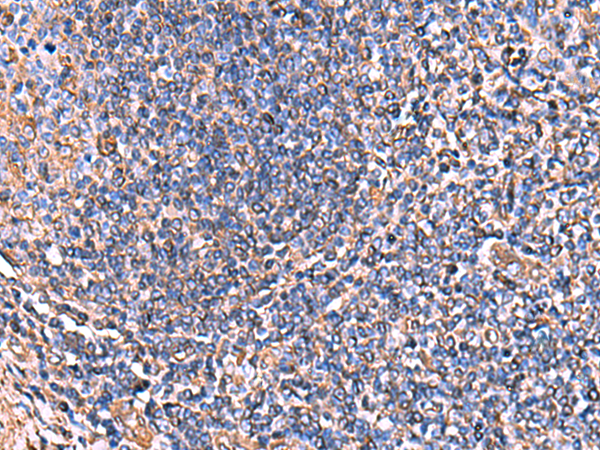

分类: 科研抗体货号: P07114别名: MSF; MSF1; NAPB; SEPT9; SINT1; PNUTL4; SeptD1; AF17q25应用: IHC反应种属: Human, Mouse, Rat